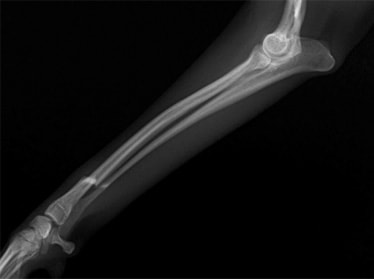

ペルシャ猫 11ヶ月齢 雄

他院にて左大腿骨遠位の成長板骨折(salter-harrisⅠ型)が認められており、治療相談を目的として来院。当院にて、キルシュナーワイヤーを用いたピンニングにより骨折部位の整復を行いました。術後の経過は良好で、現在も経過観察中です。

術後レントゲン